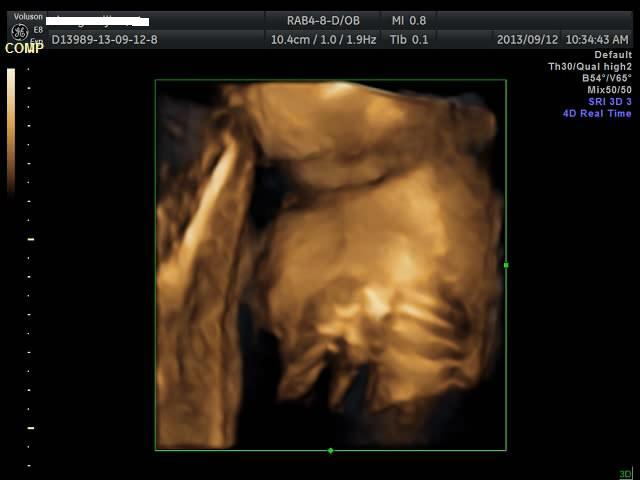

有没有能够帮我看看是千金还是帅哥的朋友?只是好奇是应该准备蓝色衣服还是应该买粉色衣服呢? 点击展开 匿名用户 2013-09-12 20:44 为您推荐: 其他回答 吓死我了... 匿名用户 2013-09-12 20:57 看不出来啊,买米黄色的吧 不论男女,都很好看 匿名用户 2013-09-12 20:57 帅哥的朋友吧,最好选粉红色的 匿名用户 2013-09-12 20:53 要怎么看才好 匿名用户 2013-09-12 20:48 千金,买粉红的 匿名用户 2013-09-12 20:47 相关问题 谁帮我看看是千金还是帅哥! 来看看我家24天的小帅哥,穿粉色衣服么么哒 张凡帅吗?很好奇听说是个帅哥,求解!!!!!!!